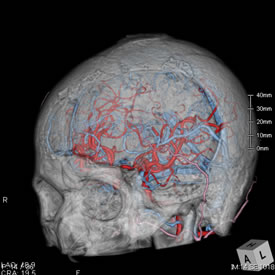

当院のMDCTで次のような画像を撮影することができます。